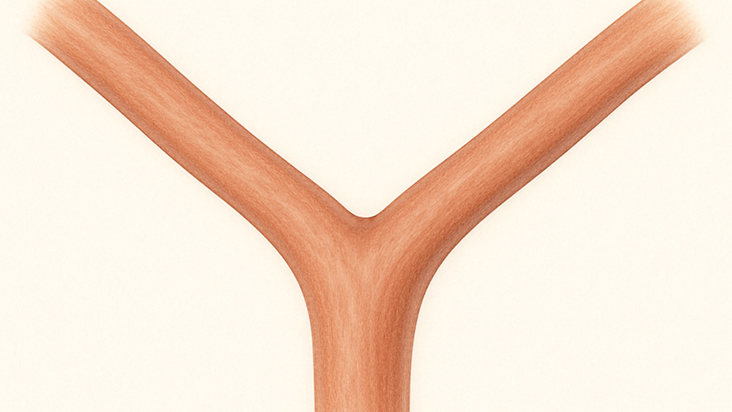

正常な脳血管

脳動脈瘤とは、脳の血管(動脈)の一部が風船のように膨らんで、こぶのようになった状態を指します。この「こぶ」が破裂すると、「クモ膜下出血」という命に関わる重篤な状態を引き起こします。